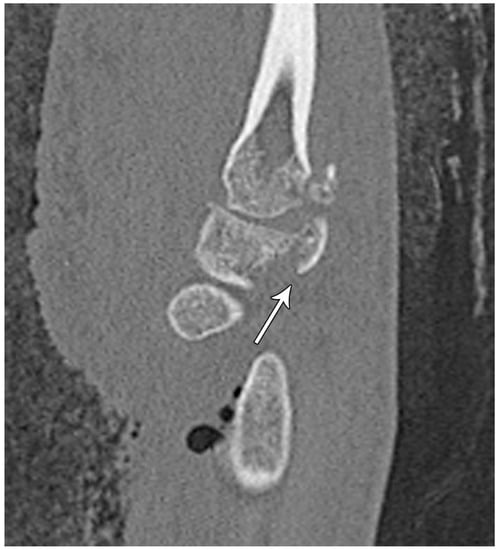

Figure 16. Sagittal reformatted CT of the wrist showing transarticular lunate fracture (arrow).

Lunate fractures are categorized as volar pole, dorsal pole, transverse, osteochondral, and transarticular (Figure 16). Volar pole lunate fractures are the most common and are due to the axial compression from the capitate with the wrist in dorsiflexion and ulnar deviation and additionally may lead to volar intercalated segment instability (VISI) [23]. Like the scaphoid and capitate, the proximal lunate is susceptible to vascular compromise in trauma, with up to 20% of people having only a single palmar nutrient artery supplying the entire lunate. Management of stable, nondisplaced lunate fractures consists of 4–6 weeks of immobilization. Surgical management is indicated for displaced fractures and those with concomitant scapholunate ligament or lunotriquetral ligament injury to preserve the existing anatomy and ensure stability. Chronic fractures with advanced arthritis may even call for partial fusion or proximal row carpectomy [10].